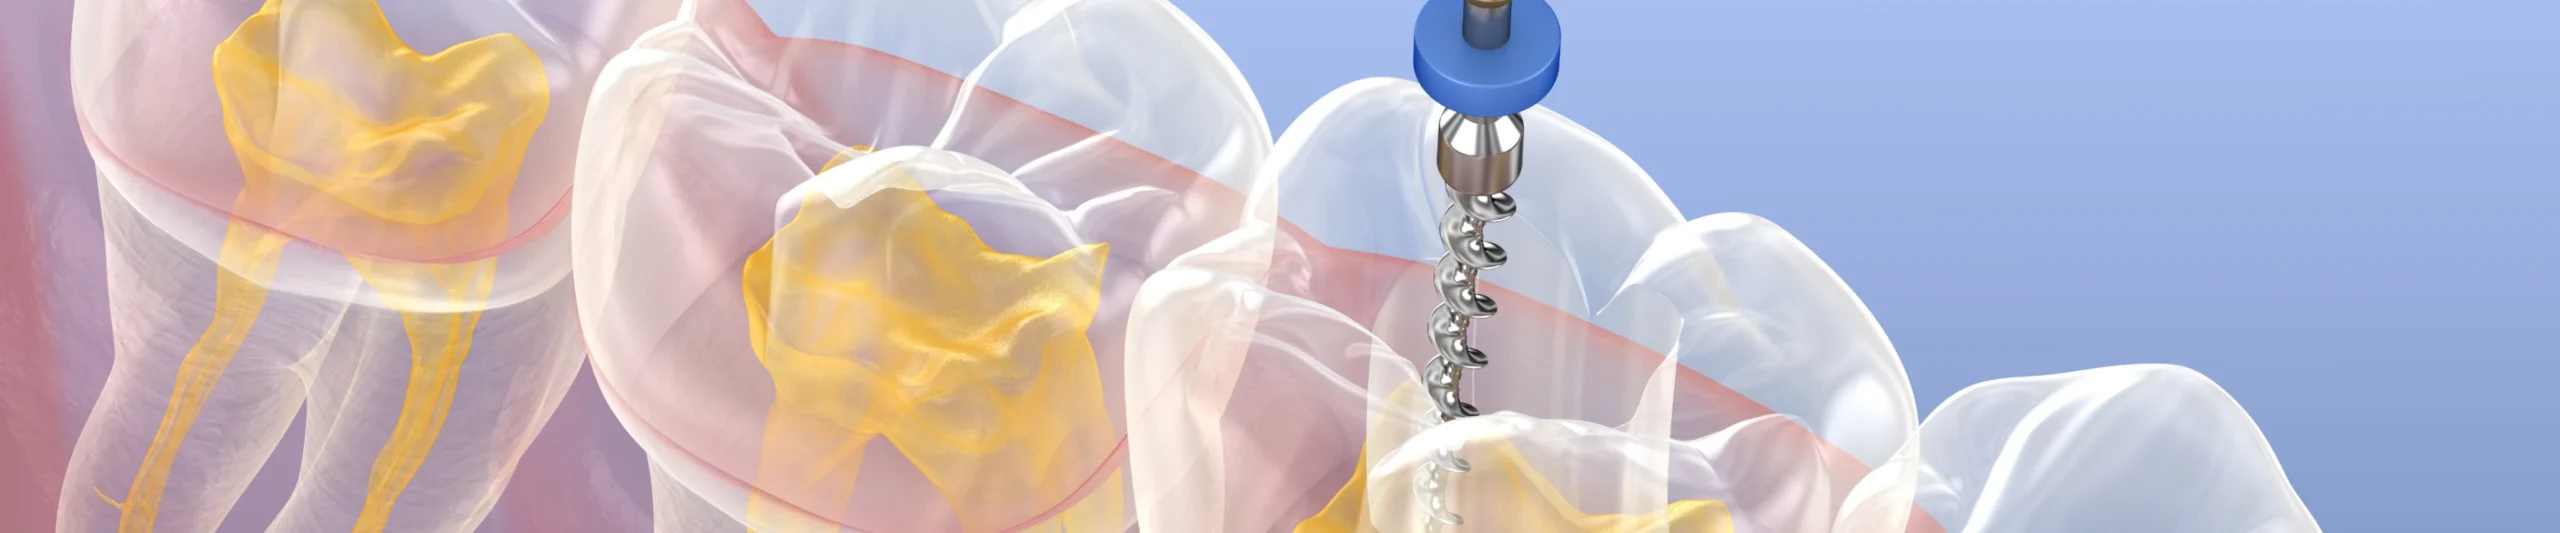

L’endodontie est une spécialité dentaire qui se concentre sur le traitement des infections à l’intérieur des dents, notamment des canaux radiculaires. Lorsqu’une carie profonde ou un traumatisme atteint la pulpe dentaire, un traitement endodontique est nécessaire pour éliminer l’infection et préserver la dent. Le traitement consiste à nettoyer et désinfecter les canaux, puis à les obturer pour éviter toute réinfection.

Grâce aux avancées technologiques, telles que les microscopes opératoires et les instruments de précision, l’endodontie moderne permet de traiter les cas les plus complexes avec un taux de succès élevé. Ce soin permet de soulager la douleur tout en maintenant la structure naturelle de la dent, évitant ainsi des extractions et préservant l’intégrité de l’arcade dentaire.

L’endodontie consiste à soigner l’intérieur de la dent, notamment le canal radiculaire, pour éliminer l’infection et soulager la douleur, tout en conservant la dent naturelle.